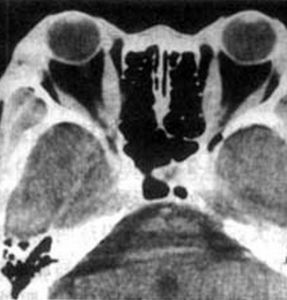

TAO的影像學檢查有一定特徵。CT表現為多條眼外肌或單一眼外肌呈一致性梭形腫脹,其肌腱止點正常,此點是與眼外肌炎的重要區別。眶尖部高密度影是TAO CT掃描的另一特徵性表現,是由多條腫脹的眼外肌在眶尖匯集所致眼眶B型超聲可見多條眼外肌粗大及球後脂肪墊增厚。